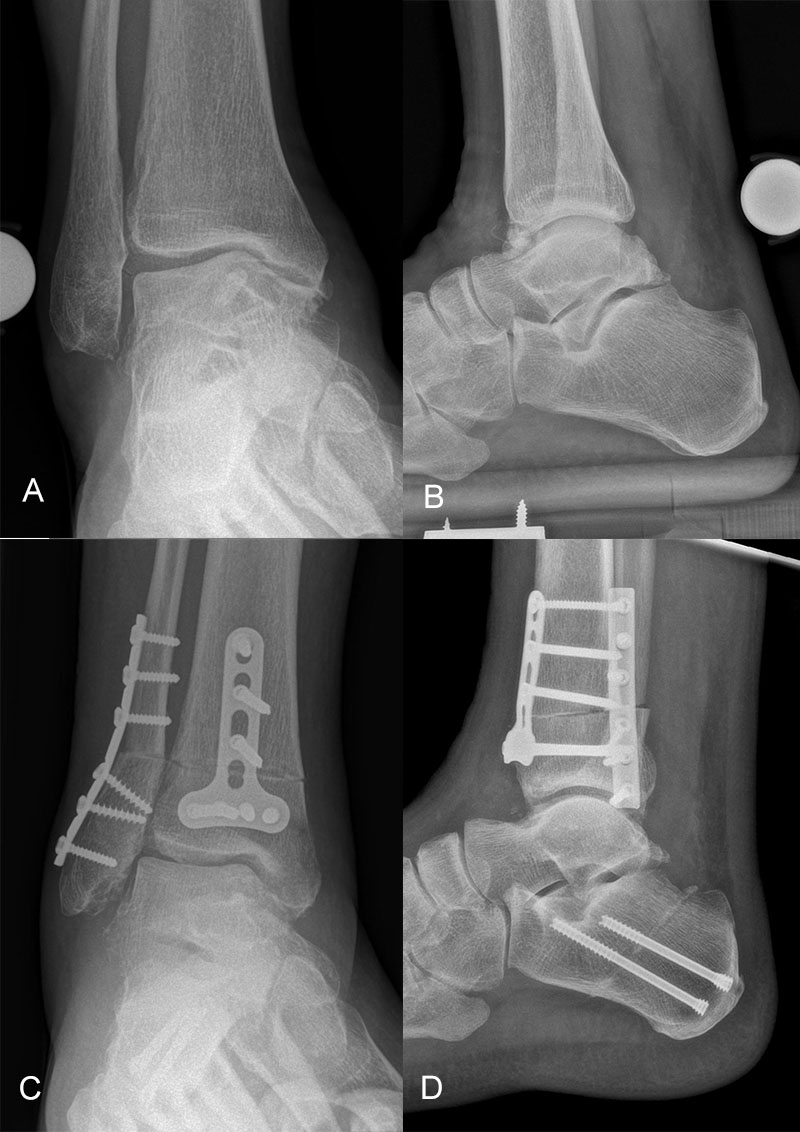

Native Röntgenaufnahmen des Sprunggelenks in 2 Ebenen unter Belastung (antero-posterior und lateral) erlauben Gelenkspaltverschmälerung, osteophytäre Anbauten sowie Achsfehlstellungen zu beurteilen. Eine „Canale-Aufnahme“ (Pronation des Fußes von ca. 15 °, Röntgenstrahl 75 ° nach kranial) 9 kann hilfreich sein, die subchondralen Oberflächen einzusehen. Die korrekte Abbildung der Sprunggelenkgabel in der sogenannten „Gabel-Aufnahme“ (mortise-view) ist zudem notwendig zur Beurteilung der Gelenkkongruenz. An Grenzen stößt die konventionelle Röntgenaufnahme allerdings bei OCLs ohne weitere knöcherne Veränderungen. Bis zu 50% der OCLs sind auf konventionellen Röntgenaufnahmen nicht sichtbar. Auch kann der Zustand des Knorpels nicht beurteilt werden 10. Bei Achsfehlstellungen werden zusätzlich Rückfußachs-Aufnahmen (Saltzman View) angefertigt bzw. eine Einbeinstandaufnahme zur Bestimmung der Becken-Bein-Achse.

Zur Vollansicht und zum Lesen der Bildbeschreibung bitte das Bild anklicken.

Der Computertomographie (CT) fehlt ebenfalls die Fähigkeit, den Knorpel direkt zu bewerten. Mit dem CT können jedoch weitere Details der knöchernen Verletzung, wie Größe, Form, Umfang und evtl. Dislokation der Läsion beurteilt werden 11. Insbesondere kleine Knochenkanten oder Gelenkkörper lassen sich in der CT wesentlich besser darstellen als mit einem MRT.